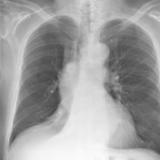

RLL Collapse 1 PA